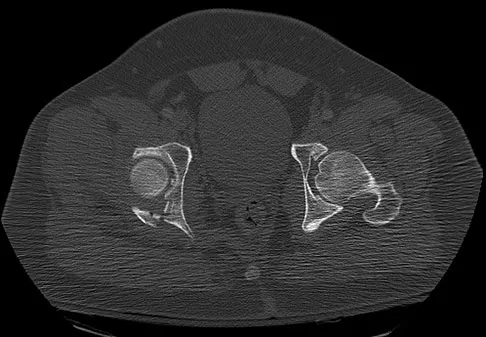

Which of the following findings best describes the acetabular fracture shown in Figure 38?

Explanation